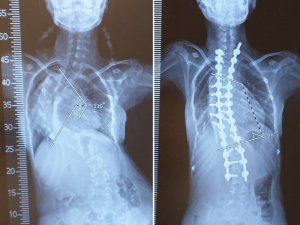

Mersinli skolyoz hastası Medine, ameliyatla yeniden doğdu